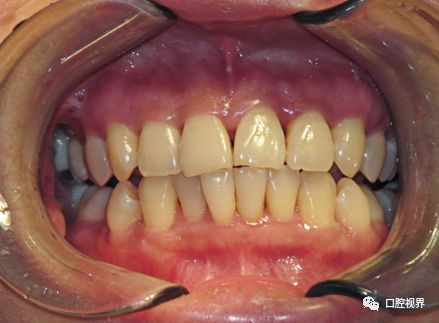

牙列畸形

牙列畸形会随着时间变得愈发严重。

譬如,牙齿原本就存在倾斜的状态,后期因为无数次的咬合使得牙齿倾斜程度越发严重,从而导致牙齿的缝隙也越来越大。